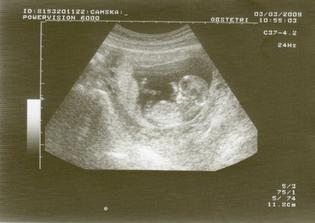

♥ 3.3.2009♥ Vypadá to, že vše je OK 🙂 Maminka i tatinek jsou šťastný, akorát brouček je trošku lenoch. Vůbec se nechtěl hýbat, jenom mával.